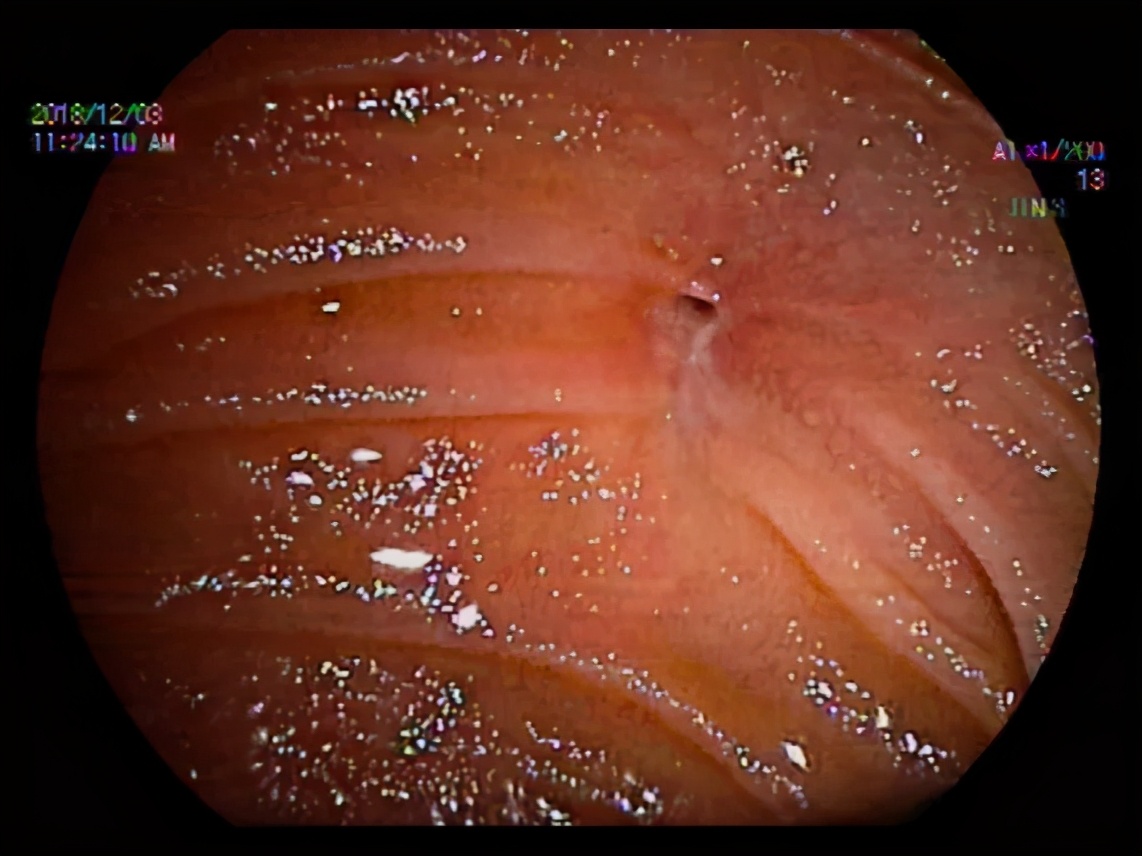

(历经30分钟,医生终于找到“胆肠吻合口”)

我们仔细地探查了小肠的每一处,足足找了30分钟,才终于把这个针眼大小的出口找到,取出一些泥沙样的结石,然后再把出口扩大。——消化内科张迎春副主任医师